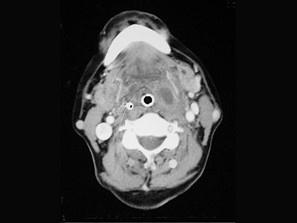

问题 患者,男性,23岁,发热头痛3天,伴咽旁和颈部剧痛,吞咽困难,吐字不清,查体:扁桃体及咽侧壁突向咽腔,但无明显充血,CT检查结果如下图:患者最可能的诊断为 ( )

选项 A、咽后脓肿 B、以上都不是 C、扁桃体周脓肿(前上型) D、扁桃体周脓肿(后上型) E、咽旁脓肿

答案 E